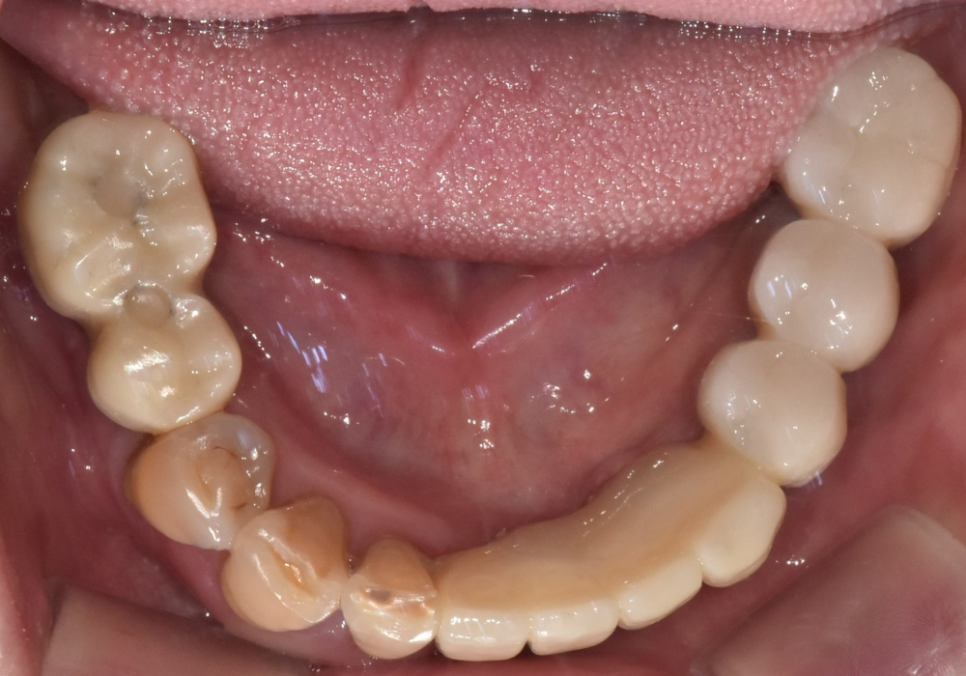

이분은 위아래 부분 틀니를

오랫동안 사용해오셨는데,

어느 순간부터 아래 틀니가 자꾸 들썩거리며

씹는 게 불편하다며 내원하셨어요.

검사 결과, 틀니를 지탱해주던

남은 치아 9개 중 무려 6개가

잇몸 질환으로 인해 심하게 흔들리고 있었습니다.

환자분과 상의 끝에 안 좋은 치아들을 정리하고

디지털 가이드를 활용해

총 7대의 임플란트를 심어

아래 전체 치아를 재건하기로 했습니다.

임플란트가 뼈와 단단히 붙은 것을

확인한 뒤에는 마지막 치아 모양을

만드는 과정을 진행했어요.

이때도 입안 가득 고무 같은 재료를 넣고

굳을 때까지 참아야 하는

번거로운 본뜨기 대신

구강 스캐너를 사용했습니다.

덕분에 재제작없이

보철이 완성되었네요^^